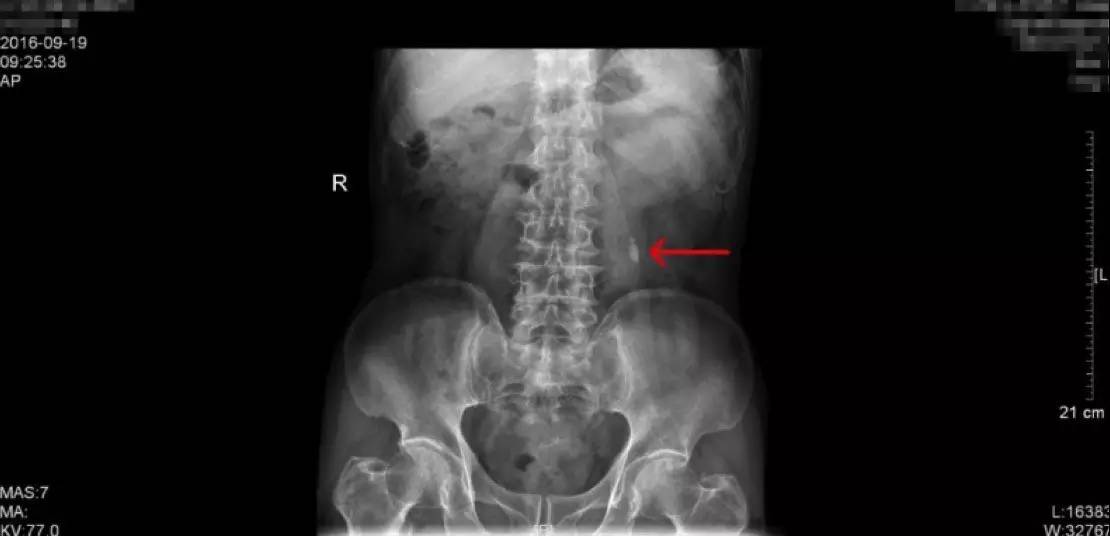

KUB检查报告:结石最大为1.2cm

KUB这一检查是泌尿系结石的常规检查之一,学名称为泌尿系平片,一般是指患者在经过肠道准备后(前一天服用泻药,让肠道内容物排出,第二天禁食,以减少肠道内容物对影像的干扰),在X线透视下摄片,涵盖整个泌尿系统,包括肾、输尿管、膀胱区域,观察这一区域有无阳性结石(酸性结石,尤其纯的酸性结石在X下无法显现,我们称为阴性结石,这一检查就无法看到,但比较少)。这一患者的KUB检查片子如上,可以看到,阳性结石表现为白色的强化,就是片子中红色箭头所指的地方,一般患者手术后也要拍一张KUB,可以和术前的检查相对比,从而直观的确认手术的效果。

手术前KUB检查报告